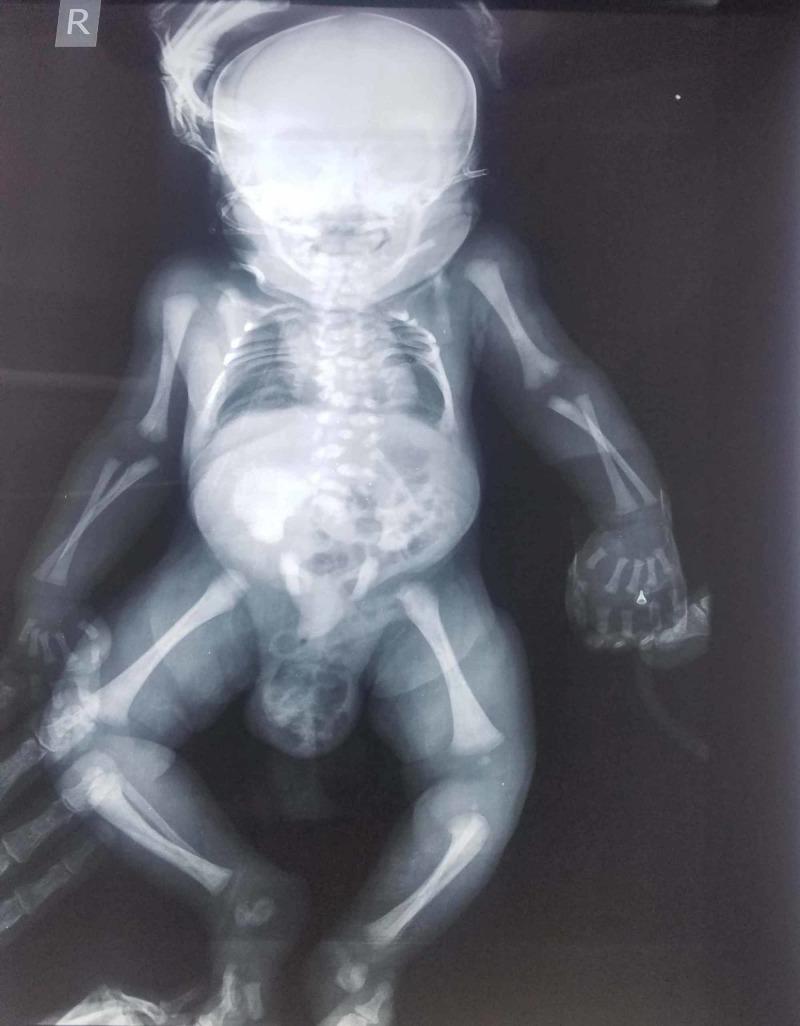

Spondyloepiphysal dysplasia (SED) is an inheritable dysplasia of the bone due to a defect in collagen. It has a prevalence of 3.4 per million. It has two important types, congenita and tarda, which are differentiated by the age presentation and heritage mode. SED congenita can present a significant reduction in the upper segment to a lower segment ratio. Collagen mutation results in abnormal growth and development of spine and limb bones. The complex pattern of craniofacial anomalies is due to defective ossification and connective tissue problem. We here present the case of a three-hour-old girl with a short trunk and craniofacial anomalies that brought in respiratory distress to the neonatal intensive care unit. This condition is rare and thus poses a major diagnostic challenge at an early stage.

脊椎骨骺发育不良(SED)是一种由于胶原蛋白缺陷导致的遗传性骨骼发育不良。其发病率为百万分之3.4。它有两种重要类型,即先天性和迟发性,可通过发病年龄和遗传方式进行区分。先天性SED可表现为上身与下身比例显著降低。胶原蛋白突变导致脊柱和四肢骨骼的异常生长和发育。颅面畸形的复杂模式是由于骨化缺陷和结缔组织问题所致。我们在此报告一例3小时大的女婴病例,该女婴躯干短小且有颅面畸形,因呼吸窘迫被送入新生儿重症监护病房。这种情况很罕见,因此在早期阶段构成了重大的诊断挑战。